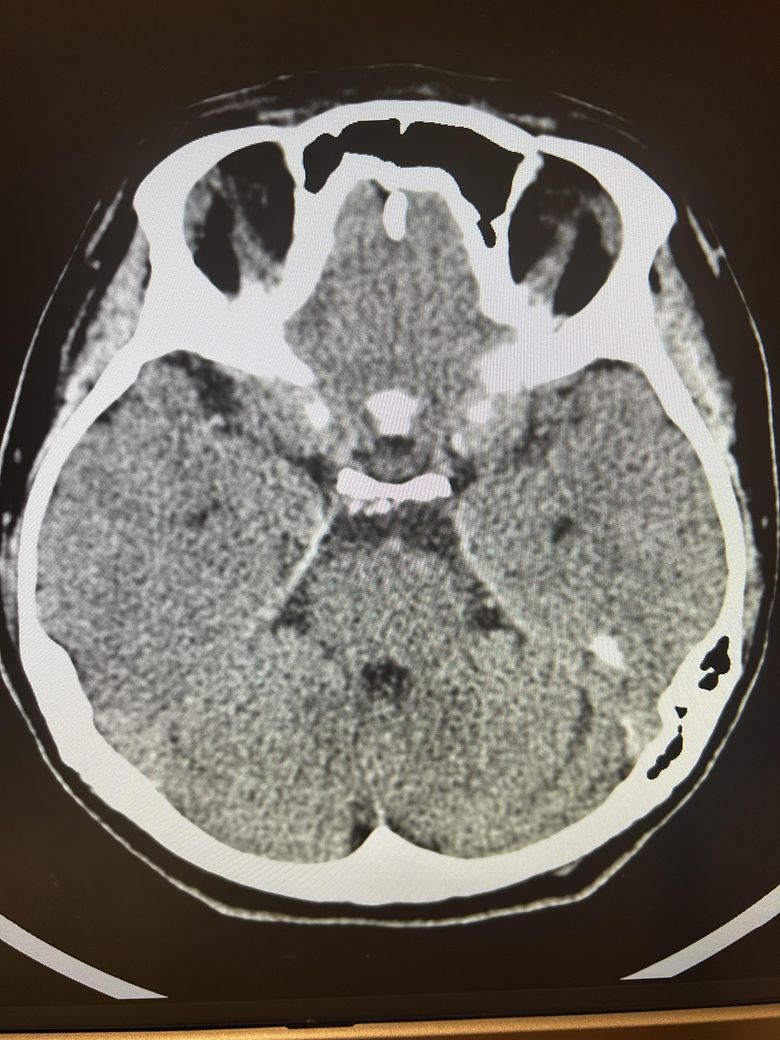

두통과 목뻐근함이 일주일째 심해서 뇌ct검사를 했습니다.

영상은 이렇게 보이는데 어떻게 의심되시나요?

석회화랑 다른것도 보이시나요?